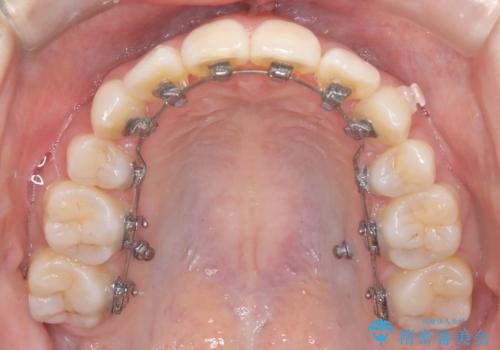

- 患者様は下顎の前歯が3本しかないという特異な歯列を持ち、噛み合わせのバランスが崩れていました。上下の歯の本数が通常と異なるため、抜歯部位の選定が重要となるケースでした。診査の結果、歯の位置や咬合のバランスを考慮し、上顎の両側小臼歯2本と左下の小臼歯1本を抜歯することで、上下の噛み合わせを整える方針としました。矯正装置は、**目立ちにくいハーフリンガル(上顎は裏側矯正・下顎は表側矯正)**を採用しました。

まず、計画通りに抜歯を行い、歯列のスペースを確保しました。上顎は裏側矯正(リンガル)で目立たないように配慮しながら歯を後方へ移動し、下顎は表側矯正を使用して、3本の前歯の位置関係を調整。上下の歯の噛み合わせを細かくコントロールしながら、全体のバランスを整えました。治療後は「歯並びがきれいになり、噛み合わせもしっかり合うようになった」と患者様にも満足していただけました。